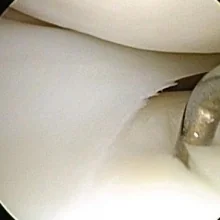

¿Te duele la rodilla? Conoce las causas más frecuentes del dolor de rodilla, opciones de tratamiento y cuándo ir al ortopedista. Guía completa para pacientes.

Guía completa sobre el dolor de rodilla, sus causas más comunes, cómo identificar los síntomas y opciones de tratamiento disponibles. Información revisada por especialistas en ortopedia.